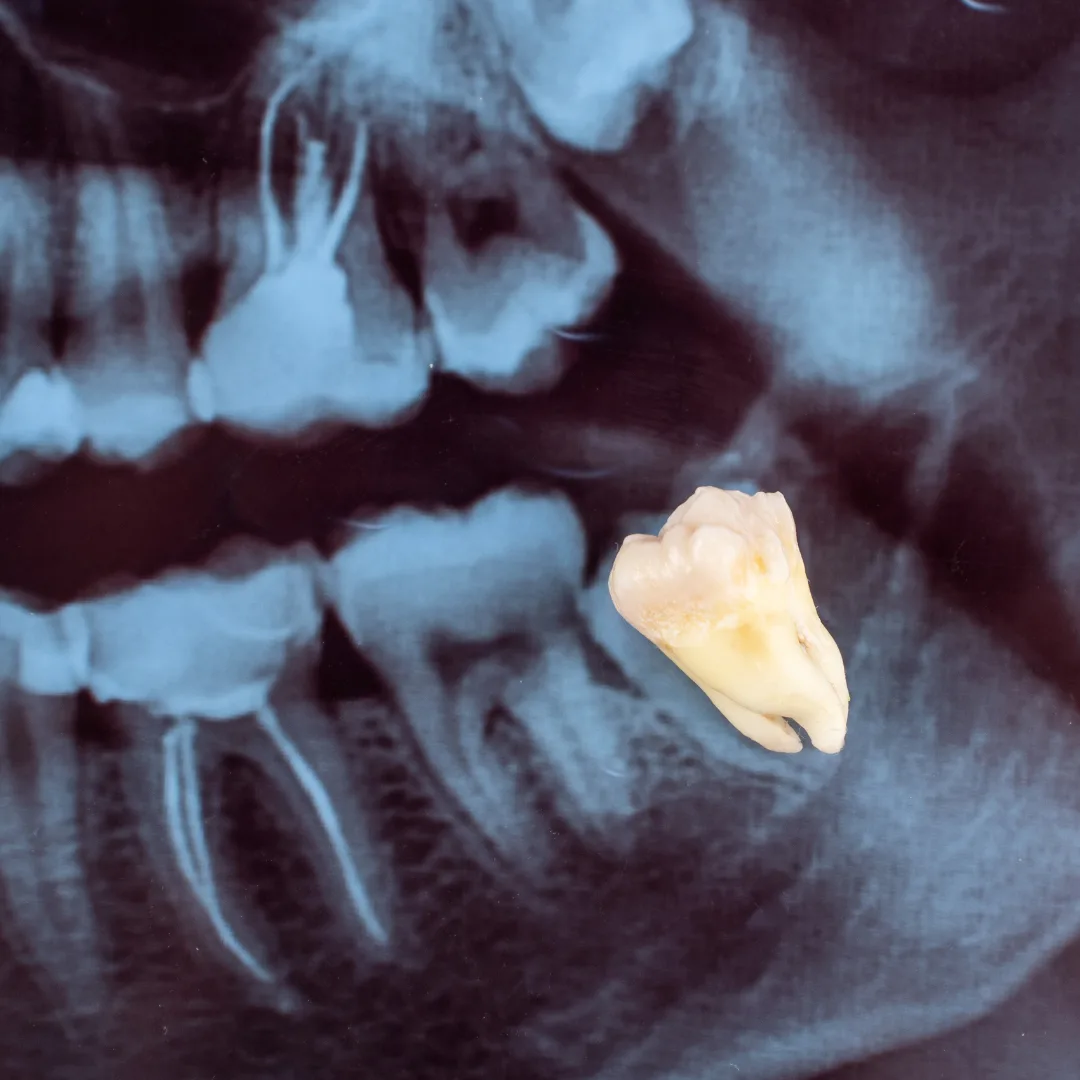

Tooth Extractions: We preserve natural teeth whenever possible because nothing is stronger or better than your original teeth. However, sometimes extraction is necessary—severe decay, advanced gum disease, or trauma can damage a tooth beyond saving. When extraction is needed, we perform it gently with attention to your comfort, healing, and post-extraction restoration options.

Tooth extraction at Thrive Dental is performed only when a tooth cannot be saved, with full emphasis on comfort and aftercare.